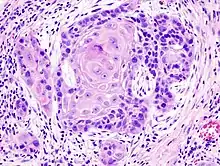

One method of classifying squamous-cell carcinomas is by their appearance under microscope. Subtypes may include:

- adenoid squamous-cell carcinoma (also known as pseudoglandular squamous-cell carcinoma) is characterized by a tubular microscopic pattern and keratinocyte acantholysis.[22]

Adenoid squamous-cell carcinoma